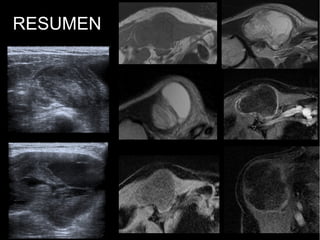

RESUMEN

RESUMEN:

Neoformación de probable

estirpe mesenquimal, con

heterogeneidad interna, alta

vascularización periferica y

necrosis central; probable alto

grado.

SARCOMA PLEOMÓRFICO

INDIFERENCIADO.

HISTIOCITOMA FIBROSO

MALIGNO.

SARCOMA SINOVIAL.

RESUMEN: Neoformación de probable estirpemesenquimal, con heterogeneidad interna, alta vascularización periferica y necrosis central; probable alto grado. SARCOMA PLEOMÓRFICO INDIFERENCIADO. HISTIOCITOMA FIBROSO MALIGNO. SARCOMA SINOVIAL. ...